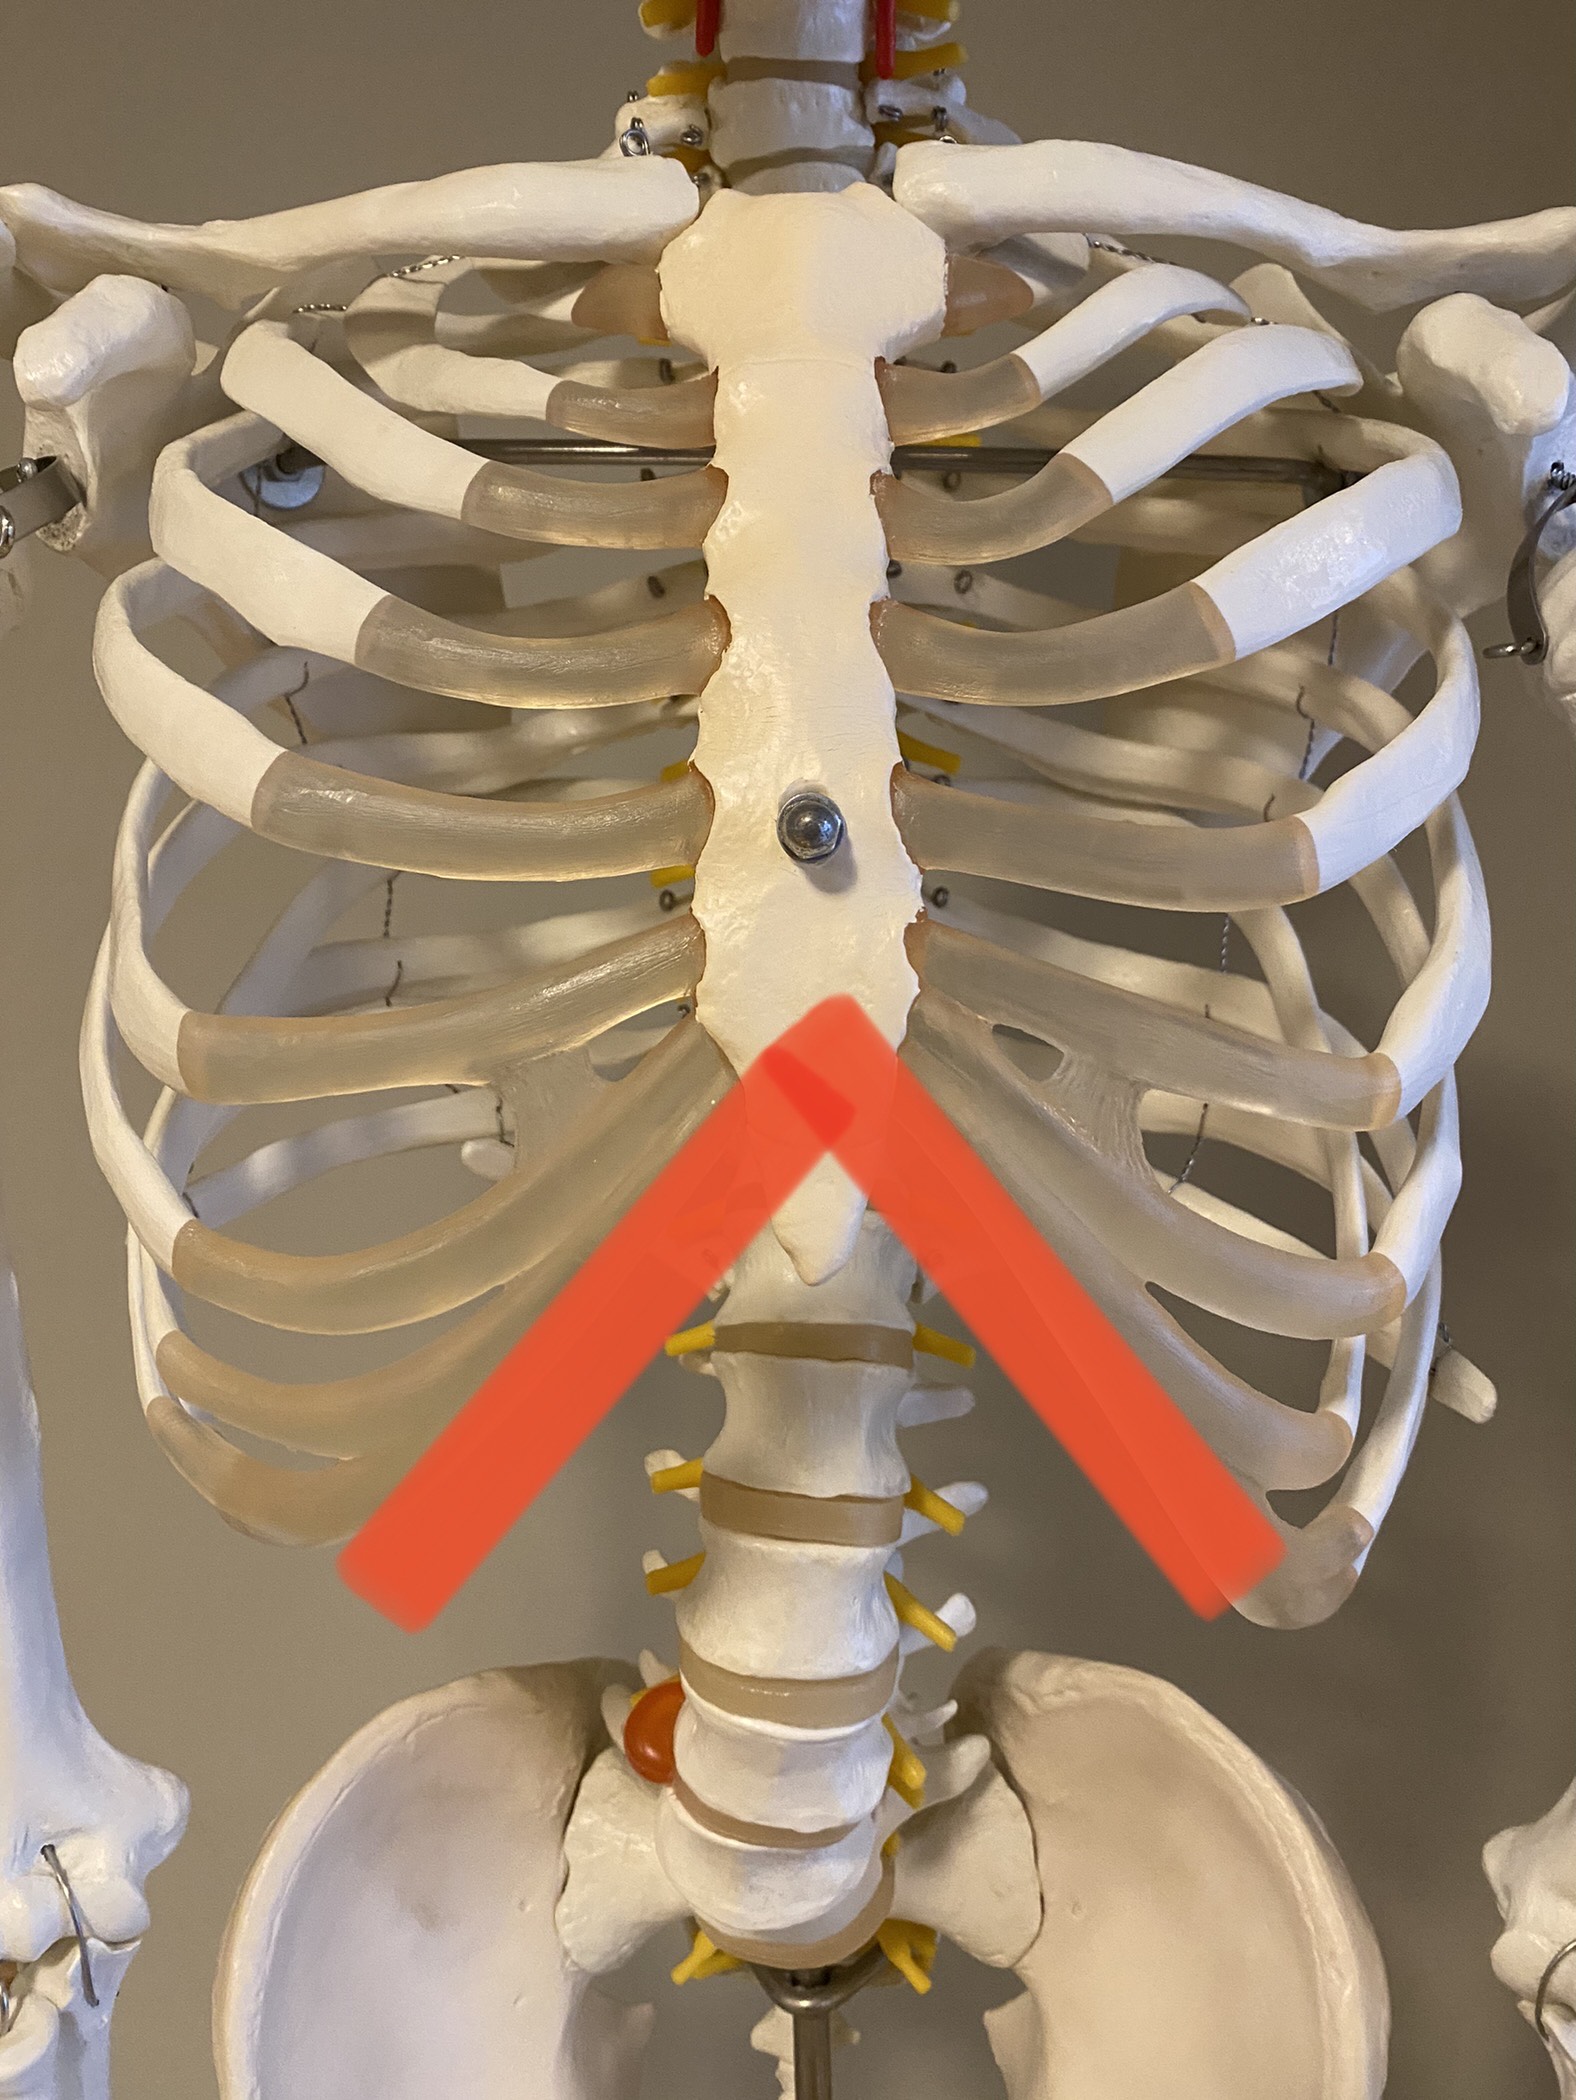

肋骨が左右に広がっている状態のことを指します。

赤ラインが90度を超えているとリブフレアと定義されています。